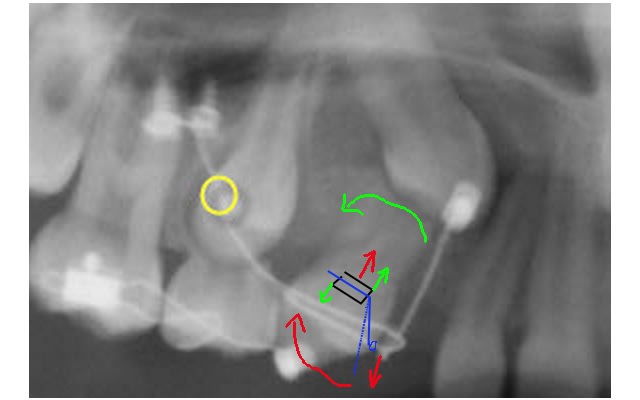

Réaliser deux danchemon sur la face vestibulaire de la 14 pour qu'un fil passant au travers puisse réaliser un couple. Jusque la ça ne change pas.

Ensuite faire passer un fil d'egiloy dans le danchemon sortant en distal (le fil se dirigera donc dans une direction apical).

Accrocher l’extrémité distal du fil d'egiloy sur la fil en TMA. La on aura :

Création d'un mouvement anti horaire sur la 14 qui nous remettra la 14 dans l'axe.

Création d'une composante vertical a direction apical sur le fil de TMA qui va supprimer la mise sous tension de la 13. Donc dancha ne vas pas vouloir de cette solution.

Donc pour modifier je fais sortir le fil d'egiloy en mesial .du danchemon avec une direction de sortie occlusal on le raccroche ensuite a la bouche du fil de TMA on aura donc

- une force en direction occlusal s'exerçant sur la boucle du fil en TMA qui maintient la force éruptive sur la canine

- une force intrusive sur la 14 mais qui sera compenser par la mise sous tension du TMA ( les minivisse s'opposant a l'expression de cette composante).

- un moment réactionnel anti horaire mettant la 14 dans l'axe